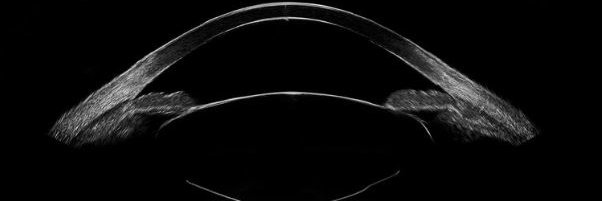

Dr. Brett Mueller, at @PNuVision , is able to get within 300 microns of their intended target when predicting post-operative vault, using the #ArcScan Insight 100. #refractive #ultrasound #ophthalmology